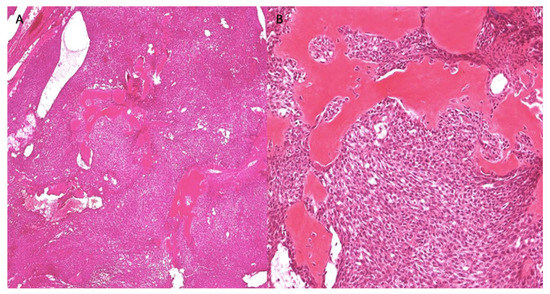

2.1. Case 1

2.2. Case 2

| Staining/IHC | PAS (+) D-labile Mucicarmine (−), p63 (+) CK5/6 (+), CK19 (+) | PAS (+) D-labile Mucicarmine (−) CK5/6 (+) | H&E only |

| Morphology | Infiltrative, non-encapsulated malignant neoplastic odontogenic epithelial proliferation with clear cell component in a dense fibrous connective tissue stroma. Neoplastic cells arranged in anastomosing trabeculae. Nuclear hyperchromasia and pleomorphism surrounded by clear, vacuolated cytoplasm. Stroma was hyalinized, densely collagenized, hypocellular, and hypovascular. | Neoplastic odontogenic epithelial proliferation diffusely infiltrated the connective tissue stroma. Neoplastic cells arranged in islands of variable size, trabeculae, and nests. Nuclei were hyperchromatic, central, and pleomorphic surrounded by clear cytoplasm. | Infiltrative odontogenic epithelial neoplasm intermixed with eosinophilic dentinoid matrix. Neoplastic cells arranged in infiltrative, non-encapsulated sheets, cords, and nests of polygonal cells with central hyperchromatic and slightly pleomorphic nuclei surrounded by clear cytoplasm and occasional pale eosinophilic cytoplasm. Occasional mitotic figures were noted. Neoplastic epithelial sheets and cords blended with eosinophilic cellular matrix without cellular rimming consistent with dentinoid deposits. |